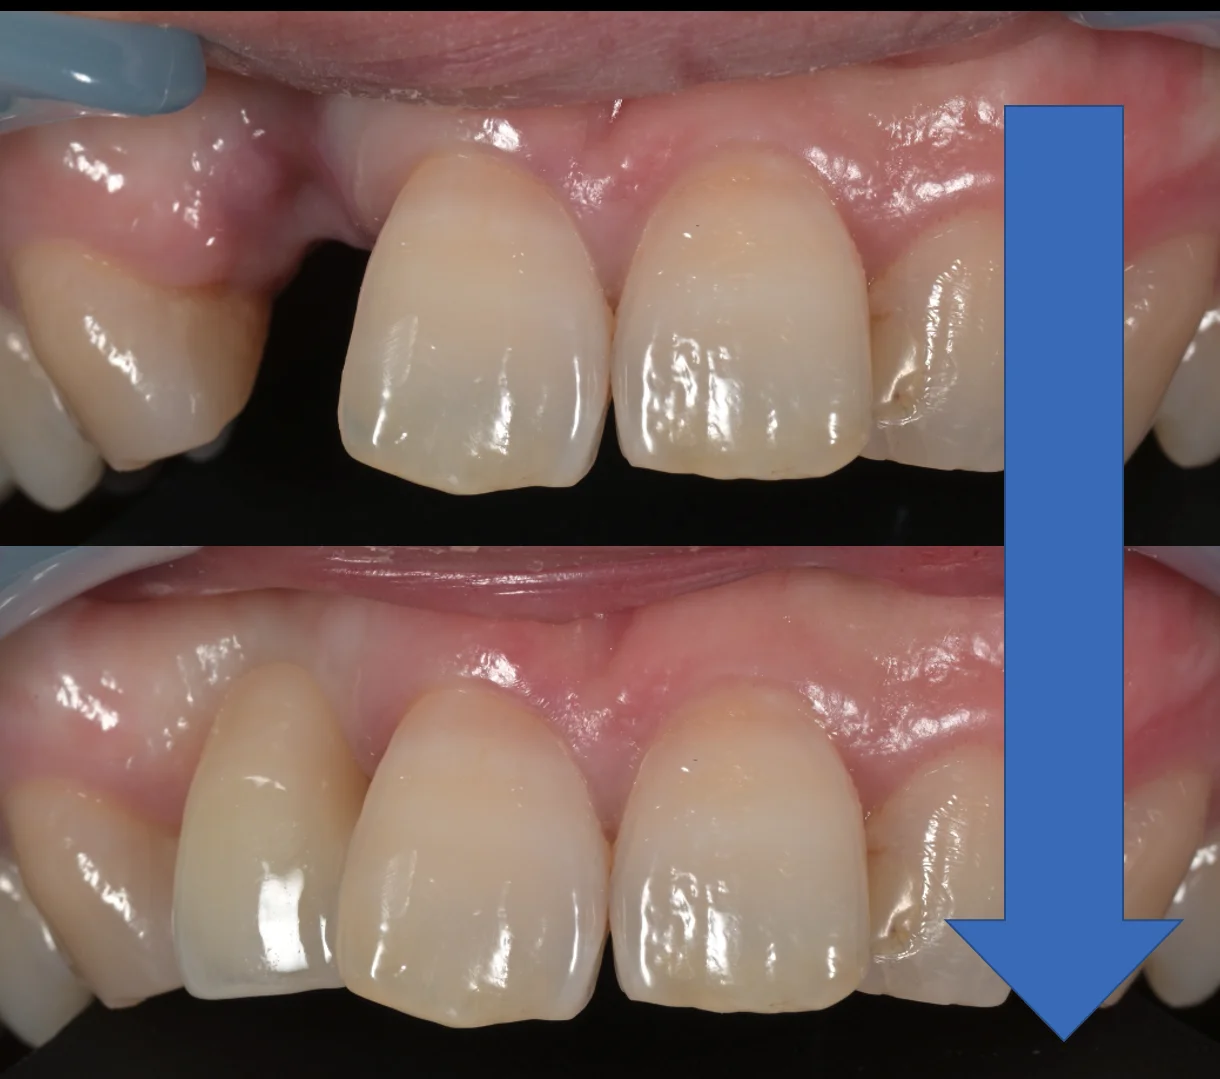

正面からの術前術後です。